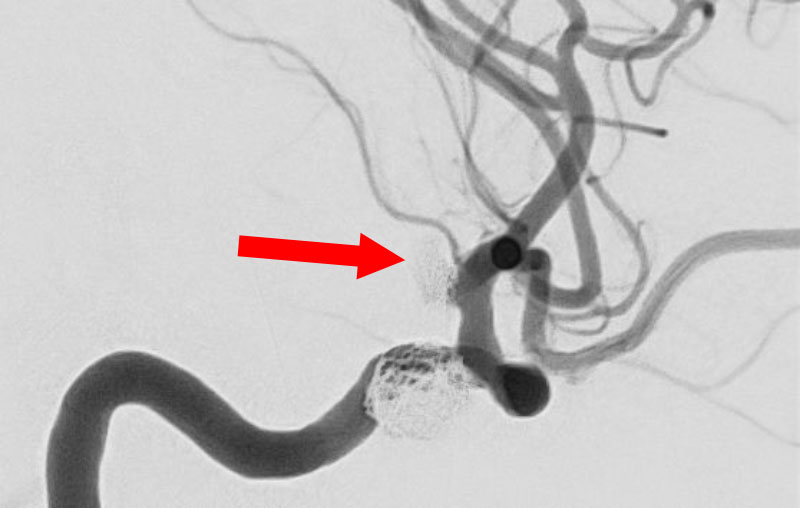

No.1596 手術中

'25年11月

左内頚動脈脳動脈瘤

60代

大阪府の病院